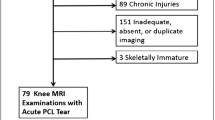

A total of 275 patients were included in the NACOX study. Eight patients only had a clinical diagnosis of ACL injury (no MRI), and the MRI scans of 13 patients were not available for analysis. Finally, a total of 254 patients (48.4% males) with a mean age of 25.4 ± 7.1 years and a mean body mass index of 23.8 ± 3.3 were included. The median (range) pre-injury Tegner activity score was 7 (2–9). Activity at the time of injury was as follows: football (37.4%), skiing (18.5%), floorball (13.4%), handball (5.9%), daily life activities (3.1%), martial arts (2.4%), basketball (2.4%), and others (16.7%).